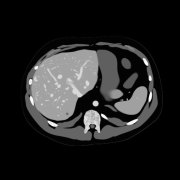

A medical imaging scientist focused on simulating x-ray imaging systems, generating synthetic 3D datasets, and developing AI frameworks for accurate, reliable, and consistent clinical imaging.

- Semiconductor detectors and photon-counting CT modeling

- Synthetic CT datasets of digital humans